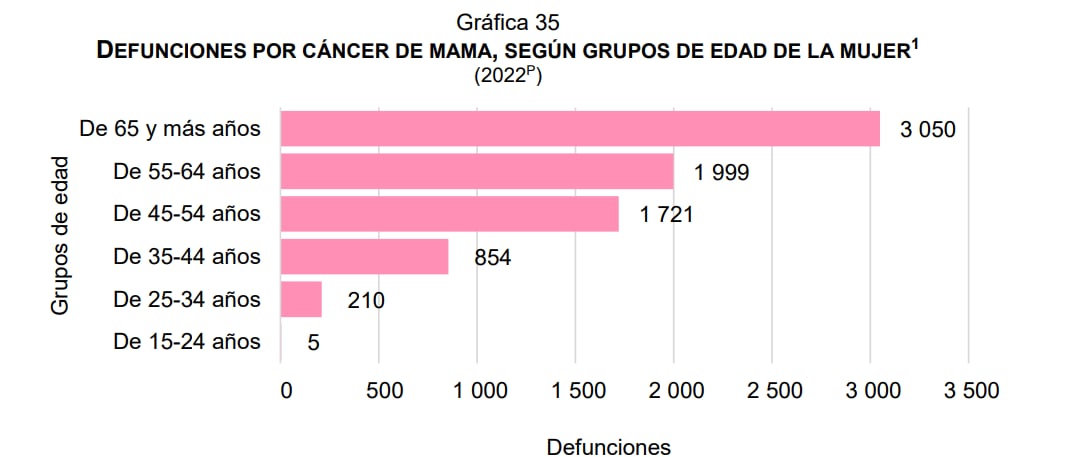

El Instituto Mexicano del Seguro Social (IMSS) señala que la edad promedio de las pacientes con cáncer de mama es de 54.9 años; aunque las estadísticas del Inegi arrojan un revelador dato: esta enfermedad no hace distingos en ningún grupo de edad, ya que en 2022, la incidencia de defunciones por dicho padecimiento fue la siguiente:

En 2022 murieron siete mil 840 mujeres a causa del cáncer de mama. Foto: Inegi

En 2022 murieron siete mil 840 mujeres a causa del cáncer de mama. Foto: InegiEl gráfico anterior demuestra que, en efecto, después de los 50 años es cuando hay mayor posibilidad de padecer cáncer de mama, pero que es importante educar desde la adolescencia para conocer los factores de riesgo -como obsesidad, falta de ejercicio, adicciones o mala identificación- e identificar síntomas a tiempo -hundimientos, abultamientos, hinchazón, cambios de color en la piel o secreciones, principalmente-.